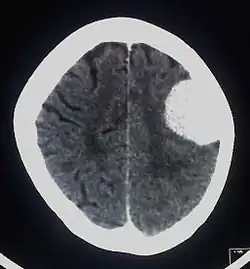

Brain tumor

The investigations completed at the Eberhard Karls University of Tuebingen in 2003 by Alfred Czarnetzki, Carsten M. Pusch and Erwin Schwaderer, showed that the owner of the skull suffered from a meningioma, which is an arachnoid tumor.[9] Meningiomas are a diverse set of tumors that arise from the meninges, which is the membranous layers surrounding the central nervous system.[10]

The slow-growing tumor had a size of 51 mm × 43 mm × 25 mm and a volume of 29 ml (1 imp fl oz; 1 US fl oz). It is believed that this tumor may have caused headaches. It is also possible that no neurological deficiencies were suffered, due to the slow growing nature of meningiomas.[9] Whether the tumor should be considered the cause of death cannot be determined from the remains. Having the rest of the skeleton would be necessary for further investigation into a possible cause of death. Meningiomas are very rare with roughly 2 out of 100,000 causing symptoms, so finding evidence of one in such ancient remains is a very exciting discovery.[11] It is the earliest evidence of a meningioma tumor on record.